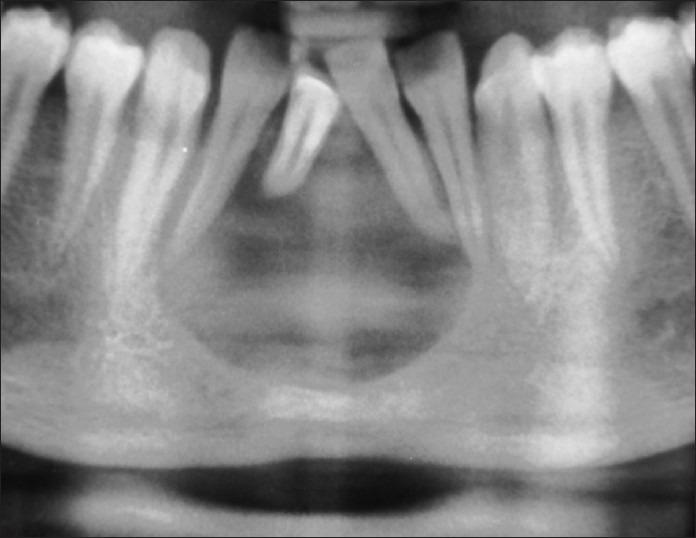

Nine different pathologies constituted the sample size of 17. A wide array of lesions was found to manifest similar signs and symptoms and radiographic findings namely ameloblastoma (three), adenomatoid odontogenic tumor (AOT, four), odontogenic keratocyst (OKC, three), ossifying fibroma (OF, two), idiopathic bone cavity (IBC, one), dentigerous cyst (DC, one), radicular cyst (RC, one), central giant cell granuloma (CGCG, one), and calcifying odontogenic cyst (COC, one).

9种不同病变构成了这17例的样本量。发现一系列病变表现出相似的体征、症状和影像学表现,即成釉细胞瘤(3例)、腺样牙源性肿瘤(AOT,4例)、牙源性角化囊肿(OKC,3例)、骨化性纤维瘤(OF,2例)、特发性骨腔(IBC,1例)、含牙囊肿(DC,1例)、根端囊肿(RC,1例)、中央巨细胞肉芽肿(CGCG,1例)和钙化牙源性囊肿(COC,1例)。